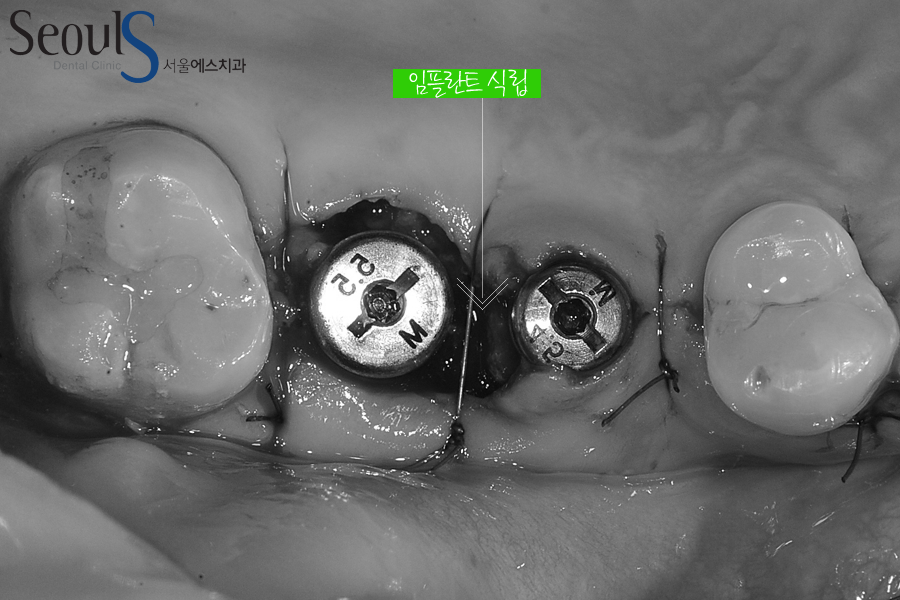

살릴 수 없는 큰 어금니 발치 후 임플란트 2개를 식립했습니다

큰 어금니의 경우 치아 주변 치조골 상태는 양호했기 때문에,

시술기간을 단축시키고, 수술을 2번 하지 않기 위해 발치 후 즉시 식립을 했습니다.

임플란트 임상을 하면서 가급적 환자분들이 편안한 치료를 받기를 바라고,

이런 즉시 식립의 경우 거기에 부합하는 치료라고 생각됩니다

다만 염증이 너무 심하거나, 치조골 흡수가 진행된 경우는 즉시 식립이 힘들고,

안전하게 2~3개월 기다린 후 임플란트 시술을 하게 됩니다.

잇몸을 꿰맨 모습으로 잇몸은 시간이 지나면 자연스럽게 아물고

임플란트란트와 잇몸뼈가 단단히 굳게 됩니다

임플란트 식립 후 임플란트의 머리 부분이 외부로 노출된 모습입니다

임플란트를 식립하기에 잇몸뼈가 충분해 식립 된 임플란트가 외부 충격에 움직일 염려가 없어

노출시킨 것입니다

만약 잇몸뼈가 부족해서 뼈이식을 했다면

임플란트가 움직이는 것을 방지하기 위해 잇몸으로 임플란트를 덮게 됩니다